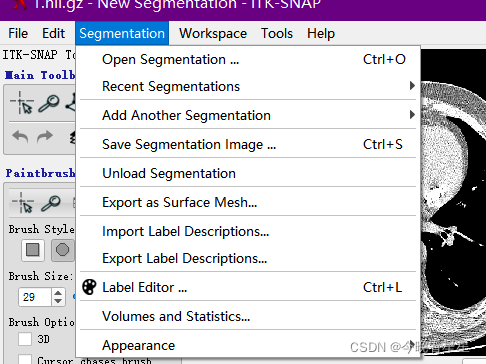

1.4 Segmentation 图像标注

Open Segmentation打开标注的文件,标注的文件为.nii格式,可以直接进行拖拽的方式来获取标注Save Another Segmentation保存标注的图像,格式为nii, 保存的标注格式,可以直接拖拽到原始图像中Unload Segmentation可以将加载的标注去掉Export as Surface Mesh将标签保存为vtk文件Label Editor对Label的相关属性进行编辑

Volumes and Statistics获取空间的统计数据

Appearence对标签进行处理,Appearence -> ToggleVisibility隐藏所有的标签,再次选择则会返回;Increase / Decrease Opacity增加/减少透明度,可以使得标签更明显